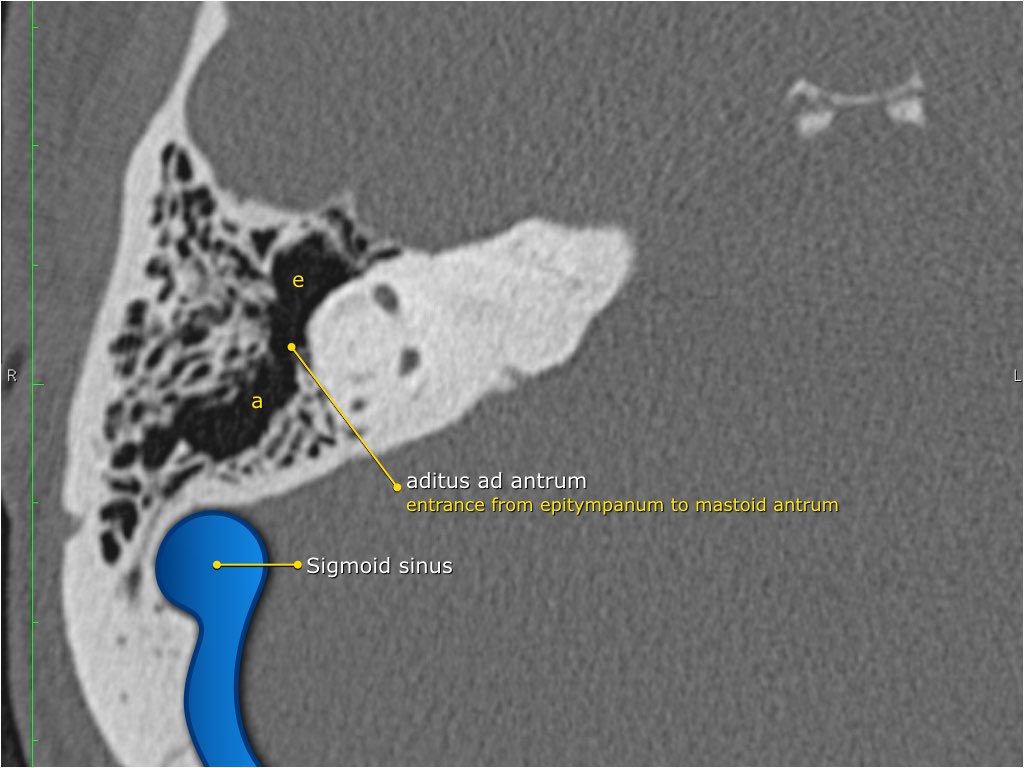

Thông qua ngách thượng nhĩ (aditus ad antrum), hòm nhĩ thông với hang chũm — một tế bào khí lớn nằm phía trên và phía sau hòm nhĩ — và thông với các tế bào khí chũm.

Thành sau

tạo nên lối vào xương chũm và được gọi là aditus ad antrum (lỗ thông hang).

Hang bào chũm (Antrum)

Hang bào chũm là một tế bào khí lớn nằm phía trên và phía sau hòm nhĩ, thông với hòm nhĩ qua ngách hang (aditus ad antrum).

Hang bào chũm được bao quanh bởi các tế bào khí chũm nhỏ hơn.